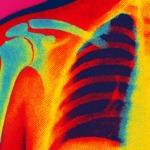

石灰沈着性腱板炎になった話【まとめ】

激痛を伴う石灰沈着性腱板炎。時間薬で耐えるしかないこの症状を耐え抜いた私の感じた事、知ったことをまとめました。